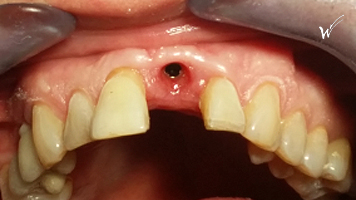

Situation clinique initiale avant traitement

L'extraction de cette dent

En raison de problèmes de rhizalyse, une résorption pathologique de la racine, ainsi que d’une infection, l’incisive centrale du patient a été extraite.

Lors de cette extraction, des biomatériaux (substituts osseux) ont été utilisés pour combler l’alvéole vidée. Il était également essentiel de réparer ou de renforcer la paroi externe de cette alvéole pour prévenir sa résorption. La finesse de cette paroi autour de la racine naturelle de l’incisive (quelques dixièmes de millimètres) ne permettait pas la pose d’un implant seul, compte tenu du vieillissement des tissus environnants et de l’importance de l’esthétique à ce niveau.